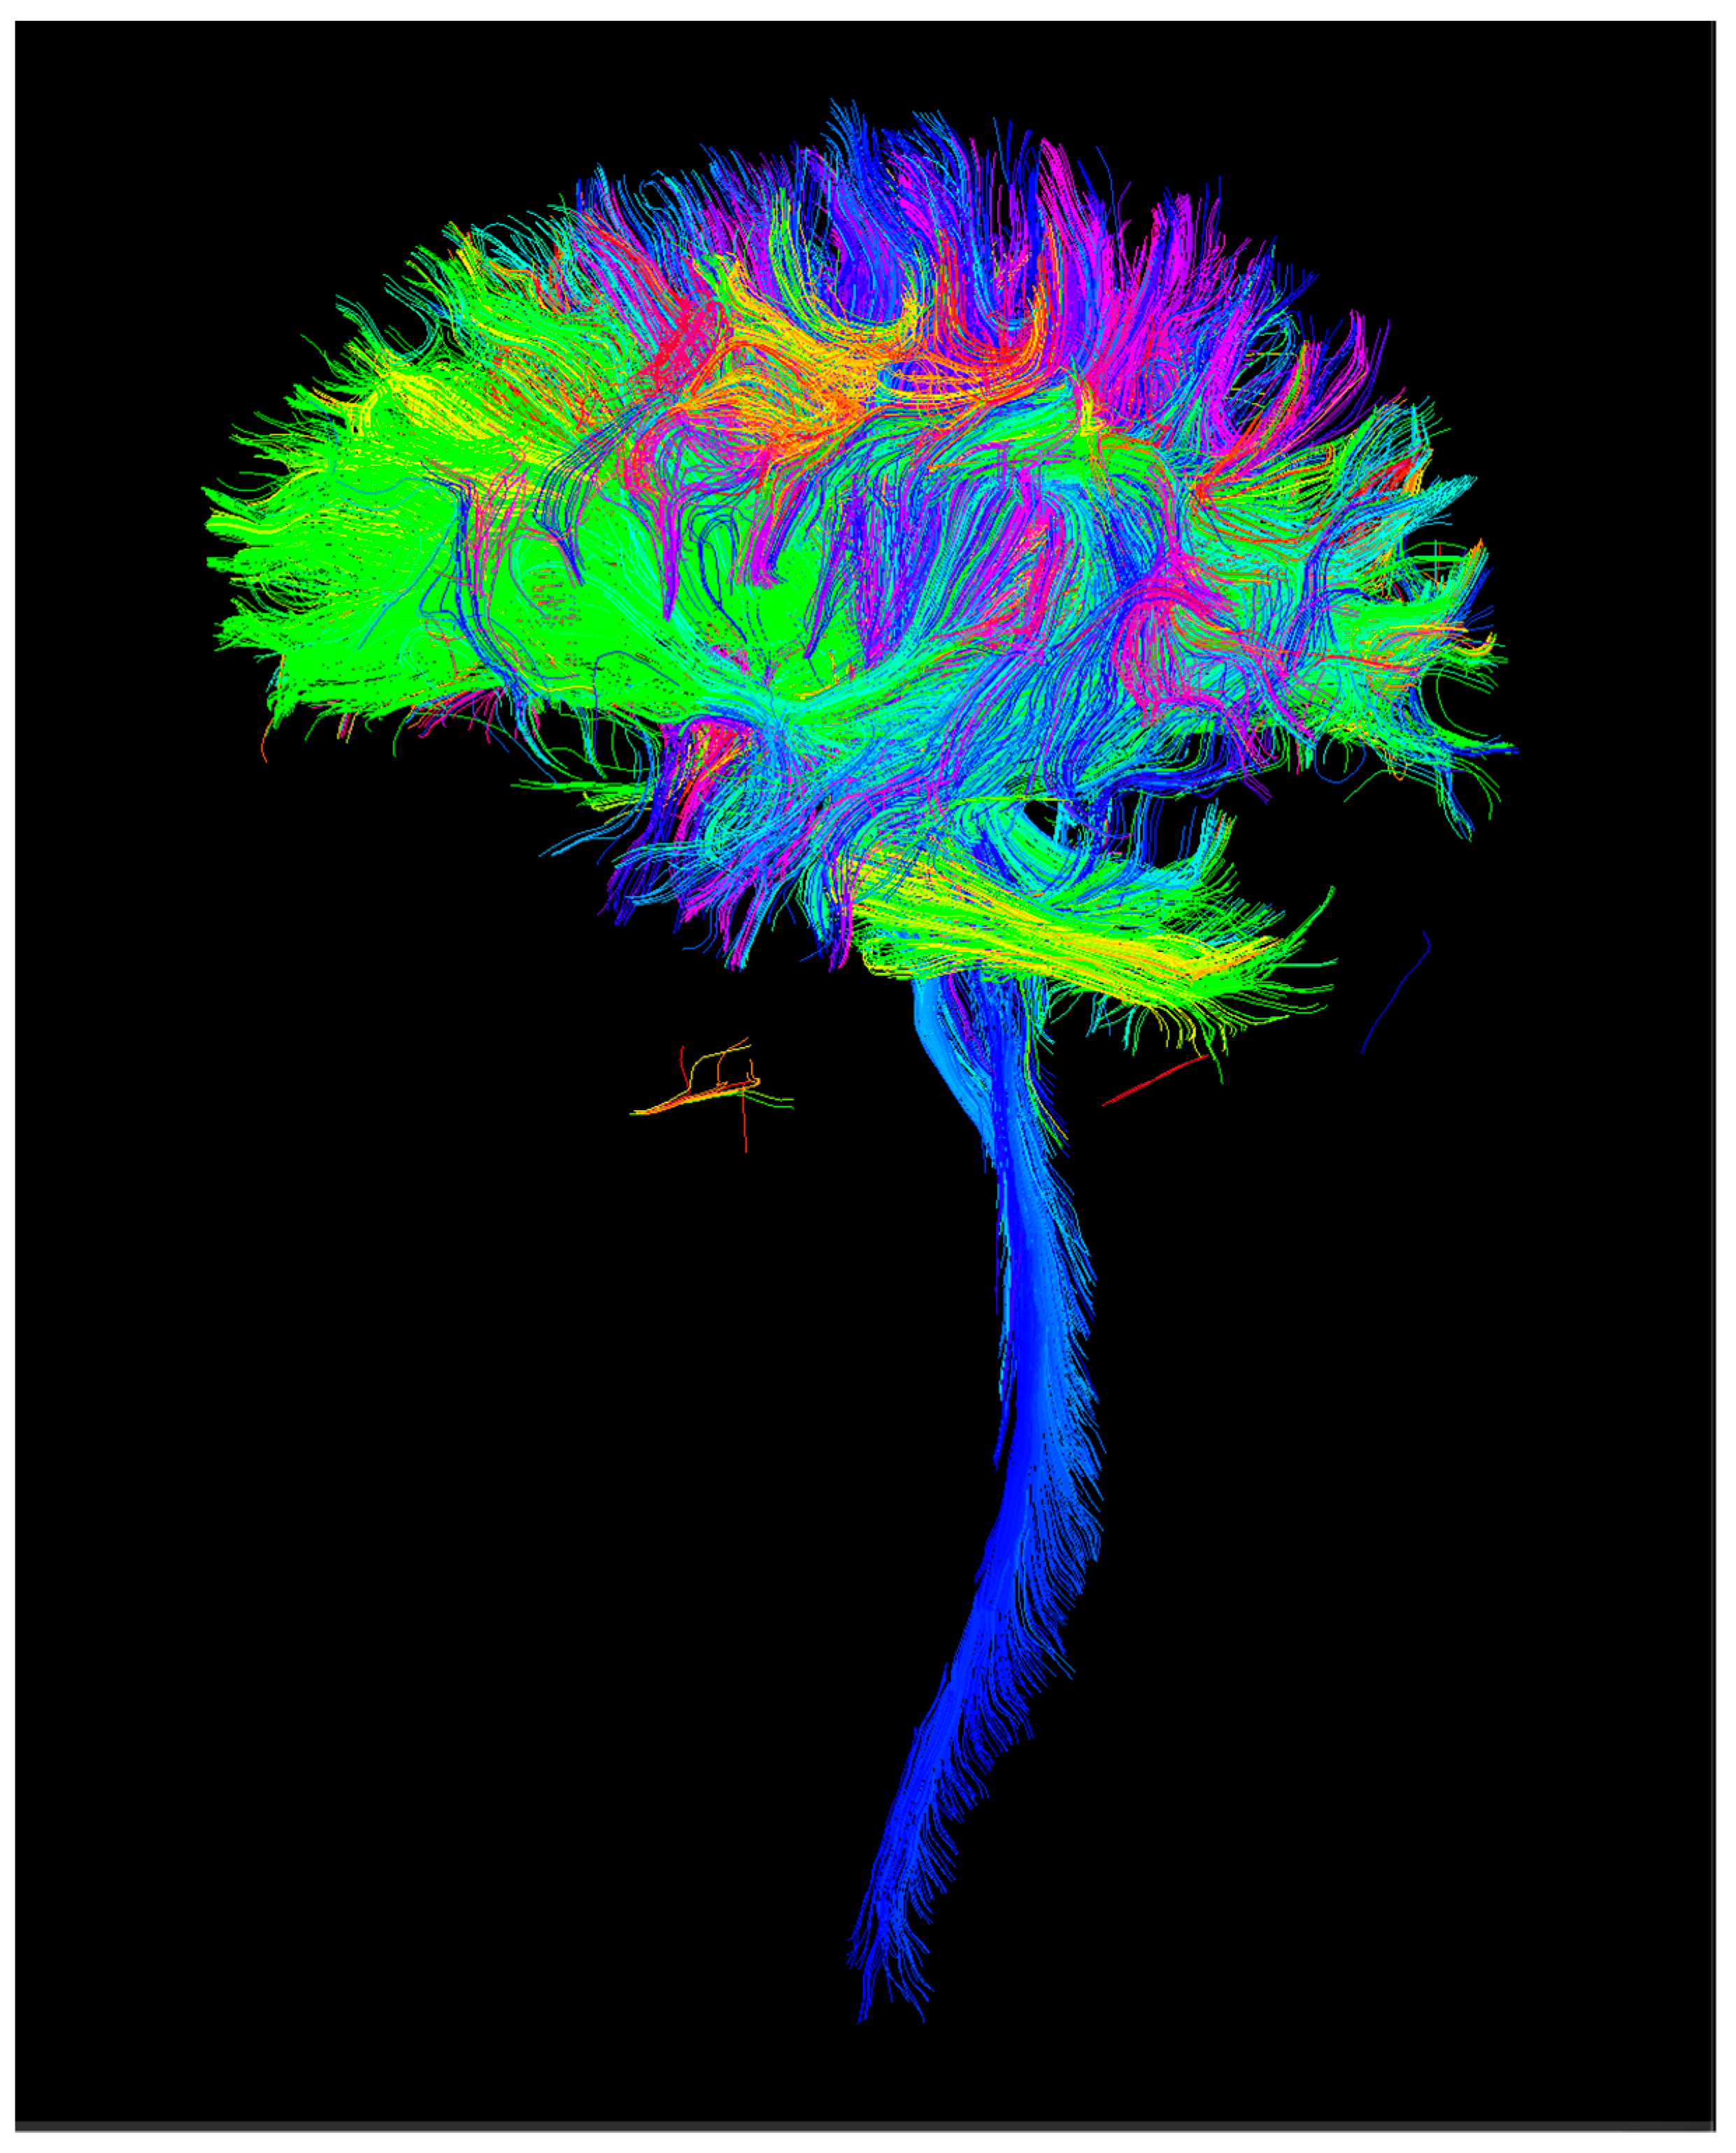

2.1.1. Image Processing

2.1.2. Connectomics

| Global connectivity | FA | 3.8·10−6 |

| Caudal-middle-frontal cortex (left hemisphere) to superior-frontal cortex (left hemisphere) | FA | <0.0092 |

| Connection of the isthmus of the left cingulate gyrus with itself | FA | <0.0092 |

| Connection of the right cerebellum cortex with itself | FA | <0.0092 |

| Left hemispheric pericalcarine cortex to itself | FA (adjusted average) | 0.003806 |

| Left superior frontal superior cortex with left putamen | FA (adjusted average) | 0.005745 |

| Right superior frontal superior cortex with itself | FA (adjusted average) | 0.008644 |

| Insula (deep temporal lobe) with itself | FA (adjusted average) | 0.008463 |

| Superoparietal cortex with itself | FA (adjusted average) | 0.003526 |

| Supramarginal cortex | Number of tractography lines | <0.0062 |